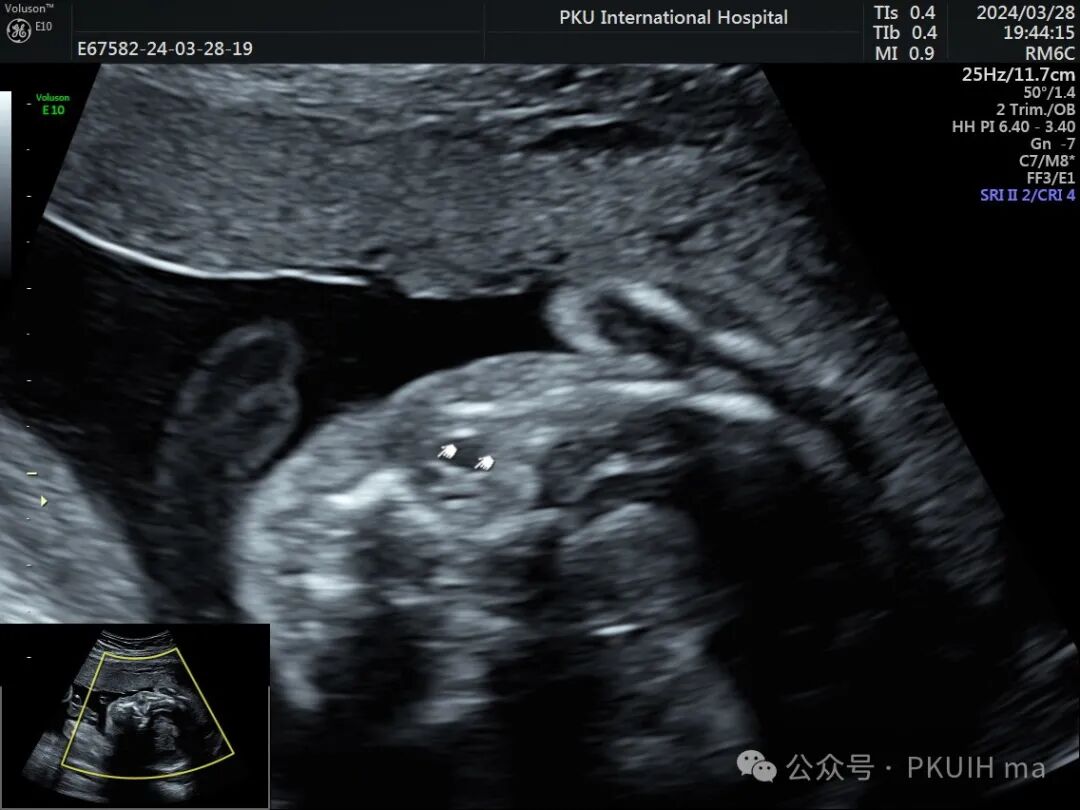

右眼球情况:两个手标分别代表晶状体和后方的永存玻璃体

实时动态观察双眼发育不对称,右眼小;两侧眼球内晶状体、玻璃体均可见,右侧晶状体小,晶状体后缘玻璃体内见不规则的高回声区。

综合以上图像初步考虑为永存原始玻璃体增生症(PHPV)。

PHPV的超声表现:一侧眼球晶状体后方可见Y形高回声或强回声条带,或者是晶状体后方圆形或圆弧状高回声团块(直接征象);同时伴有患侧眼球小,晶状体形态异常,眼轴短,部分有玻璃体浑浊。双眼发病极为罕见,表现双层晶状体浑浊,内见不规则强回声或高回声带。CDFI:部分病例可见增生的玻璃体动脉内见血流信号。该病容易反复发生眼内出血,纤维血管性肿块的收缩可能对视网膜产生牵拉,导致视网膜脱离。因此,眼部超声表现可能会随着妊娠进展而改变。